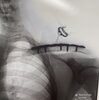

病院の様子を送って

とお願いすると

上の写真が届きました

術後のレントゲンのコピーを

いただきました

キレイに取れてホットしています